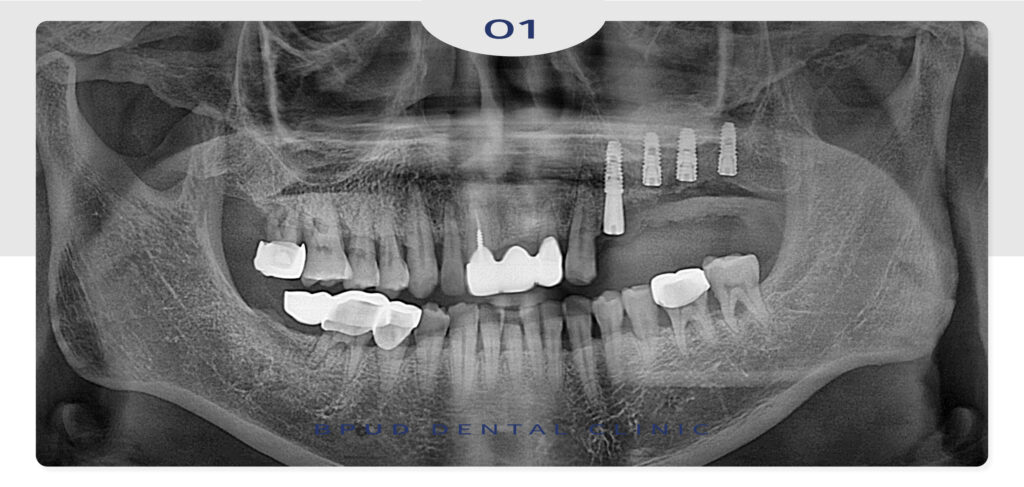

오늘은 골흡수가 심하게 진행된 부위

상악동 거상술을 동반한 임플란트 식립과

앞니 파절로 인해 상실된 부위를

임플란트로 회복하신 환자분을

소개해 드리려고 합니다.

25.07.21

이후 오래된 앞니 보철이 빠지셨다며

다시 한번 내원해 주셨는데요.

내부적으로 우식이 진행되어

파절된 상태로 치아의 동요도까지 보여

심미적인 이유에서나 장기적인 예후 측면에서

발치 후 뼈이식을 동반한 임플란트 식립을

진행하기로 하였습니다.